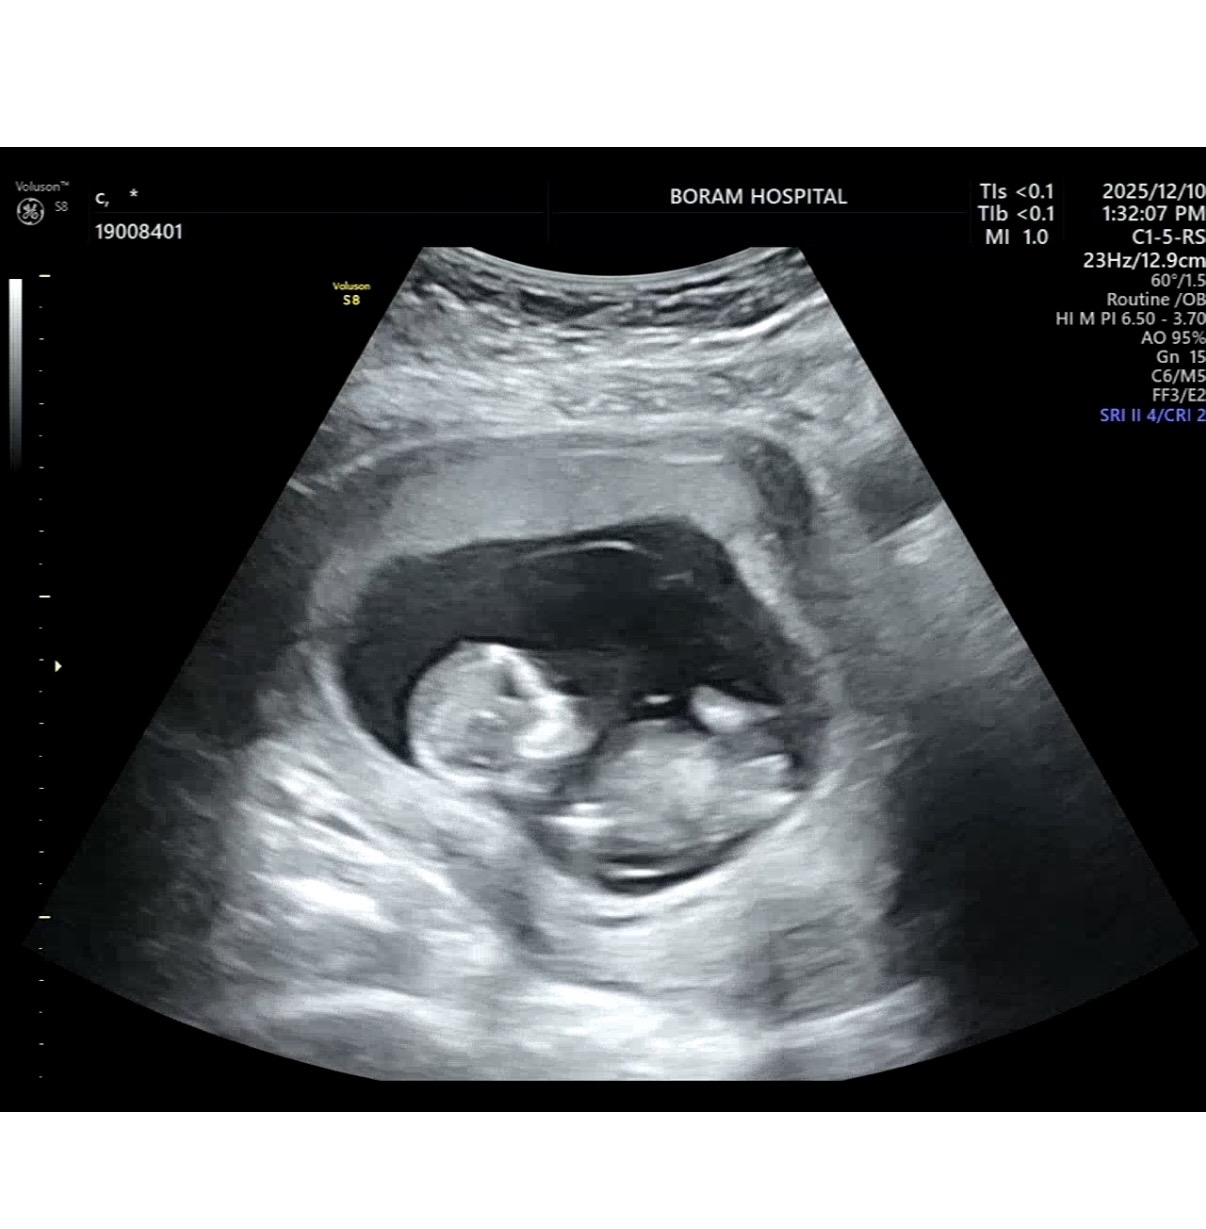

12주 성별 투표 부탁드려요🥹

12주2일 성별 투표부탁드려용